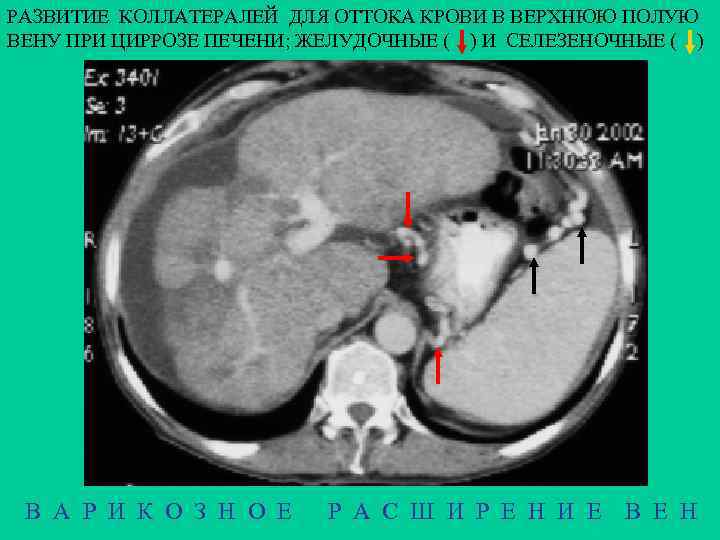

ВАРИКОЗНОЕ РАСШИРЕНИЕ ВЕН ПИЩЕВОДА 8% ВСЕХ ВСКРЫТИЙ МОРФОЛОГИЯ Расширение вен в подслизистом слое с образованием узлов. Слизистая истончается и эррозируется. В своде желудка варикозные вены появляются раньше, чем в пищеводе, но выявляютс труднее – обычно с помощью эзофагогастроскопии ЭТИОЛОГИЯ 1 - портальная гипертензия (цирроз печени), поражаются свод желудка и нижние сегменты пищевода, 2 - сердечная декомпенсация, поражение пищевода на всем протяжении 3 - сдавление верхней полой вены, поражаются верхние сегменты 4 - врожденные расширения КЛИНИКА - кровотечение (для всего ЖКТ: 1 место - язва, 2 - рак, 3 – варикозные вены) Rg Множество краевых дефектов наполнения различной формы и размеров. Рельеф деформирован. При пробе Вальсальвы узлы уменьшаются, при пробе Мюллера - увеличиваются В А Р И К О З Н О Е Р А С Ш И Р Е Н И Е В Е Н

РАЗВИТИЕ КОЛЛАТЕРАЛЕЙ ДЛЯ ОТТОКА КРОВИ В ВЕРХНЮЮ ПОЛУЮ ВЕНУ ПРИ ЦИРРОЗЕ ПЕЧЕНИ; ЖЕЛУДОЧНЫЕ ( ) И СЕЛЕЗЕНОЧНЫЕ ( ) В А Р И К О З Н О Е Р А С Ш И Р Е Н И Е В Е Н

С V Н L А НАТИВНОЕ ИССЛЕДОВАНИЕ С V Н ВАРИКОЗНОЕ РАСШИРЕНИЕ ВЕН ПИЩЕВОДА ПРИ ЦИРРОЗЕ ПЕЧЕНИ А Н V L С - аорта - печень - верхняя полая вена - селезенка - сердце L А КОНТРАСТНОЕ УСИЛЕНИЕ В А Р И К О З Н О Е Р А С Ш И Р Е Н И Е В Е Н